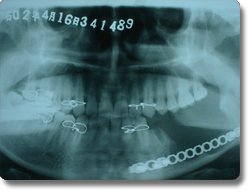

下颌骨肿瘤的手术治疗以往均采用口外颌下区皮肤切口,面部遗留疤痕。我科学习国外的先进方法,运用先进的手术器械,采用经口腔内切口入路方法,对下颌骨良性肿瘤,先行肿瘤切除,再同时采用钛合金成型再造板行下颌骨肿瘤切除后骨缺损缺损的一期修复。该方法的优点是下颌骨肿瘤的切除和骨组织修复再造均经口腔内切口一次手术完成,不再作面部皮肤切口,满足了患者的美容需要。该治疗方法与国际最先进水平保持同步。 |